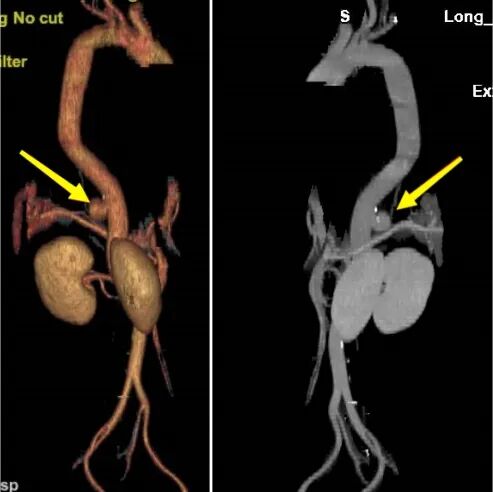

近日,在貴陽市公共衛(wèi)生救治中心骨外科與貴州醫(yī)科大學(xué)附屬醫(yī)院血管外科的攜手合作下,成功完成了一例胸椎結(jié)核合并下肢不完全性癱瘓以及胸腹主動(dòng)脈瘤的復(fù)雜病例,并且患者已康復(fù)出院。此次病例的成功救治進(jìn)一步加深了兩院之間的學(xué)科合作,并為處理類似復(fù)雜疑難病癥的多學(xué)科診療模式積累了寶貴經(jīng)驗(yàn)。 患者因“腰背痛并伴有下肢無力,導(dǎo)致無法正常行走長(zhǎng)達(dá)一個(gè)月”前往貴陽市公共衛(wèi)生救治中心骨外科就診。經(jīng)過詳細(xì)檢查,患者的下肢肌力評(píng)分僅達(dá)到3級(jí),且在臍水平面以下區(qū)域感覺明顯減退,無法站立和行走。結(jié)合影像學(xué)檢查結(jié)果,醫(yī)生考慮患者可能患有胸9-11椎體結(jié)核。進(jìn)一步檢查還發(fā)現(xiàn)患者存在腹主動(dòng)脈上段假性動(dòng)脈瘤,并且該動(dòng)脈瘤與胸9-11椎體結(jié)核病灶緊密相連。這使得胸椎手術(shù)面臨術(shù)中大出血的風(fēng)險(xiǎn)(圖1-4)。

圖1.圖2:術(shù)前見腹主動(dòng)脈瘤與胸9-11椎體病灶緊密相連 圖3.圖4:動(dòng)脈瘤術(shù)前三維影像 面對(duì)這一復(fù)雜病情,貴陽市公共衛(wèi)生救治中心骨外科迅速與貴州醫(yī)科大學(xué)附屬醫(yī)院血管外科進(jìn)行溝通,共同決定采取聯(lián)合手術(shù)治療方案。在兩家單位共同努力下,患者成功進(jìn)行了降主動(dòng)脈-腹主動(dòng)脈覆膜支架腔內(nèi)隔絕術(shù)。手術(shù)后,患者的腹主動(dòng)脈瘤得到了有效控制,血管外科團(tuán)隊(duì)也順利完成了血管修復(fù)工作(圖5-6)。 圖5.圖6:降主動(dòng)脈-腹主動(dòng)脈覆膜支架腔內(nèi)隔絕術(shù)術(shù)后 隨后,貴陽市公共衛(wèi)生救治中心骨外科對(duì)患者實(shí)施了“胸椎結(jié)核病灶清除+椎體次全切除+鈦籠植骨融合+椎弓根螺釘內(nèi)固定術(shù)”(圖7-11)。手術(shù)成功地完成了胸椎結(jié)核病灶的清除,并進(jìn)行了脊柱的重建。目前,患者已經(jīng)能夠下地行走,下肢的感覺也得到了恢復(fù)。 圖7.圖8.圖9:胸椎結(jié)核術(shù)后影像 圖10.圖11:術(shù)后三維影像 “患有腹主動(dòng)脈瘤和胸椎結(jié)核的病人相對(duì)罕見,治療過程復(fù)雜且手術(shù)風(fēng)險(xiǎn)高,需要多學(xué)科的緊密合作。這次病例的成功治療,充分體現(xiàn)了貴陽市公共衛(wèi)生救治中心骨外科與貴州醫(yī)科大學(xué)附屬醫(yī)院血管外科之間的高效醫(yī)療協(xié)作和專業(yè)實(shí)力,同時(shí)也為處理類似復(fù)雜疾病提供了珍貴的臨床經(jīng)驗(yàn)?!辟F陽市公共衛(wèi)生救治中心骨外科脊柱組組長(zhǎng)任鵬醫(yī)師表示,“跨學(xué)科的聯(lián)合治療,能夠很好地應(yīng)對(duì)復(fù)雜病情,提高治療的成功率,切實(shí)為人民群眾提供安全優(yōu)質(zhì)的服務(wù)?!?/p> 貴陽市公共衛(wèi)生救治中心骨外科簡(jiǎn)介 貴陽市公共衛(wèi)生救治中心外一科(骨外科)成立于2009年11月,是省內(nèi)唯一的骨與關(guān)節(jié)結(jié)核??萍案腥竟强?。在過去的十年中,成功治療了約4500例骨結(jié)核患者,診療效果和服務(wù)享有較好口碑。目前,科室已擴(kuò)展為三個(gè)亞??平M:脊柱組、關(guān)節(jié)創(chuàng)傷組和頭頸外科組。開展脊柱、關(guān)節(jié)等骨感染疾病、頸部疾病以及骨折、脊柱關(guān)節(jié)退行性疾病、骨腫瘤手術(shù)等治療。此外,科室還負(fù)責(zé)HIV相關(guān)骨科疾病的診治工作。 患者可根據(jù)個(gè)人需求選擇骨科專家門診或普通門診服務(wù),骨外科提供全天候24小時(shí)的醫(yī)療服務(wù)。目前,科室開展了一系列具有挑戰(zhàn)性的手術(shù)治療,包括復(fù)雜脊柱(頸胸腰)、關(guān)節(jié)結(jié)核手術(shù)、四肢關(guān)節(jié)創(chuàng)傷及椎體成形術(shù)、初次人工全髖關(guān)節(jié)置換術(shù)、初次復(fù)雜及人工髖關(guān)節(jié)翻修術(shù)、初次人工膝關(guān)節(jié)置換術(shù)、復(fù)雜初次及人工膝關(guān)節(jié)翻修術(shù)、嚴(yán)重粉碎性骨盆及髖臼骨折等。此外,科室還涵蓋綜合醫(yī)院骨科大部分常見、多發(fā)疾病的手術(shù)及保守治療??剖遗鋫淞酥行虲臂X光機(jī)、電動(dòng)磨鉆、骨折治療儀、中頻/低頻治療儀、下肢CPM功能鍛煉器、空氣壓力波等多種先進(jìn)設(shè)備。針對(duì)脊柱、關(guān)節(jié)疾病患者的主要臨床癥狀,如頸肩疼痛、腰腿疼痛、四肢關(guān)節(jié)疼痛、下肢活動(dòng)障礙等,科室還開展了中藥穴位貼敷、藥棒穴位按摩、艾灸等特色中醫(yī)治療,以滿足臨床需求,為患者提供高質(zhì)量的服務(wù)。 咨詢電話:0851-85959033